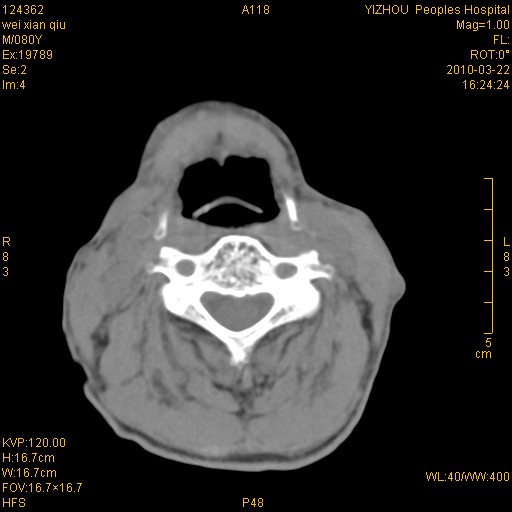

标题: CT25263:喉部占位?

男,80岁.声嘶三月余.

喉前庭右侧壁明显增厚,并见向内突出的软组织密度新生物,表面光滑,其后方软组织层次尚清晰,多考虑:喉部乳头状瘤!建议喉镜并病检!

右侧声们下区新生物